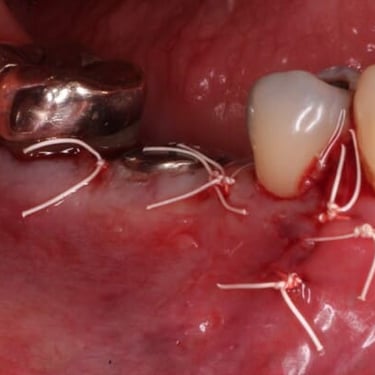

Infección postoperatoria

La infección postoperatoria es una complicación que puede ocurrir después de la colocación de un implante dental, manifestándose con dolor, hinchazón y fiebre.

Los pacientes deben estar atentos a signos de infección después de la cirugía.

El tratamiento incluye antibióticos y, en algunos casos, la limpieza quirúrgica del área afectada.